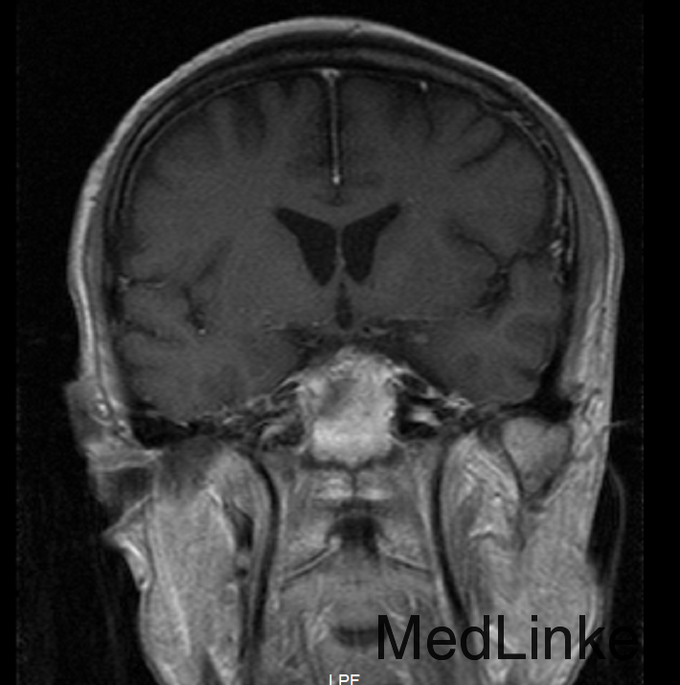

患者,男,56岁,因“右肺腺癌术后3年半余,头痛半年”入院。患者3.5年余前因肺癌在当地医院行手术治疗,术后予化疗8次,放疗32次,2年余前复查胸部CT见两肺转移。6月前患者出现头痛,不剧可忍,无视力模糊。

初步诊断:1.颅内转移性肿瘤 2.右肺腺癌术后,两肺转移。入院后完善相关检查:(2015-10-01 18:34)(急诊)血常规(血液):白细胞计数16.6×10^9/L↑、中性粒细胞百分比95.4%↑、(2015-10-01 19:19)(急诊)降钙素原(血液):C-反应蛋白217.5mg/L↑、癌胚抗原248.9ng/mL↑、癌抗原199354.0U/mL↑、癌抗原12556.0U/mL↑、癌抗原24277.8U/mL↑,(2015-10-05 14:04)行CT(胸部)检查提示:肺癌术后改变,两肺多发结节,考虑转移,较前(2014.05.05)增大、增多。入院后予邦达抗感染、甲泼尼龙40mg bid静滴减轻炎症反应,冸托拉唑40mg qd护胃,奥拉西坦4g qd修复脑神经,经治疗后患者病情好转,目前病情稳定,今予出院。